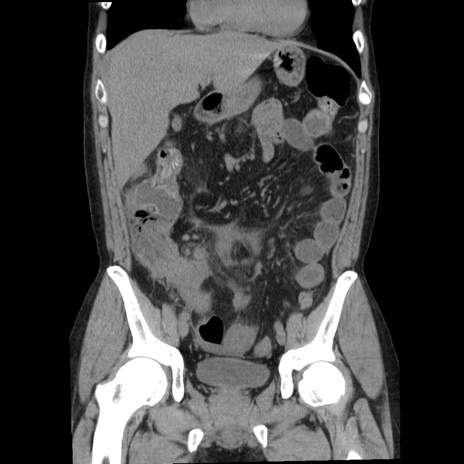

症例29(冠状断像)

【症例】40歳代男性

【現病歴】2日前から胃痛あり。徐々に周期的な激痛に変化した。本日になっても激痛があるため受診。

【身体所見】意識清明、BT 38-39℃台あり、腹部:膨満、やや硬、右下腹部に圧痛あり。

【データ】WBC 8500、CRP 23.26